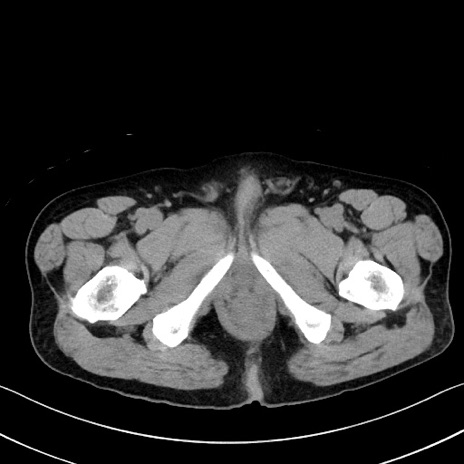

症例35(横断像)

【症例】70歳代 男性

【主訴】腹部膨満、嘔吐

【現病歴】昨日より腹部膨満感出現。本日増悪し、仙痛出現。嘔吐あり、受診。

【既往歴】糖尿病、胆摘後

【身体所見】BP 149/80mmHg、HR 74/min、BT 35.9℃、腹部:膨満、軟、圧痛なし。腸雑音減弱あり。上腹部正中切開瘢痕あり。

【データ】WBC 13500、CRP 1.72